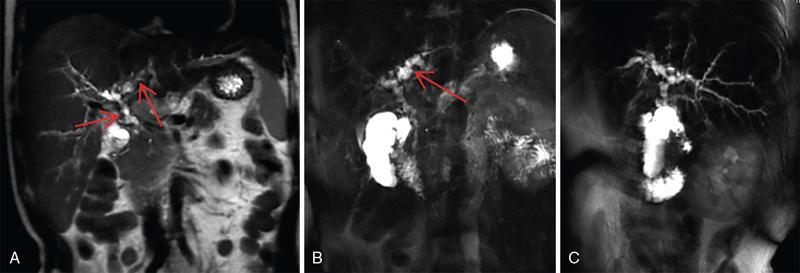

Ritu K. Kashikar, Shrinivas B. Desai, Chandresh Karnavat, Nilesh Doctor The biliary tract is subject to a variety of abnormalities. The spectrum includes benign diseases of autoimmune, infective, ischaemic, infiltrative aetiologies and malignant disorder, which most importantly represents cholangiocarcinoma. Imaging in particular magnetic resonance cholangiopancreatography (MRCP) plays a vital role in diagnosis and follow-up of these disorders. Multidetector computed tomography (MDCT) and magnetic resonance imaging (MRI) are also crucial in preoperative staging of biliary malignancies and making decisions regarding resectability and extent of resection. This chapter focuses on important benign and malignant disorders of the biliary tree and imaging features that aid in differentiation of various entities. A variety of disorders affect the biliary tree. Most biliary disorders manifest as biliary dilatation. The various causes are listed in Table 9.15.1. Imaging plays an important role in identification of aetiology based on pattern of involvement in association with clinical picture. USG is often the first investigation in a patient with jaundice. USG is excellent at showing biliary dilatation. It may be useless in assessing level of obstruction and biliary stones. Changes in liver morphology, development of cirrhosis is accurately done on USG. Early changes in conditions like primary sclerosing cholangitis (PSC), presence of intrahepatic ductal strictures, thickening of common bile duct (CBD) are, however, not confidently seen and need imaging modalities like MRCP and computed tomography (CT). Staging of hilar cancers is also best done on CT or MRI with contrast. Contrast-enhanced CT is extremely accurate in staging hilar cancers. It is a preferred modality to access radial spread of the disease and vascular involvement. Subtle changes of PSC and autoimmune cholangitis may however be missed and MRCP is preferred in these conditions. The protocol for evaluating biliary disease is standard plain scan followed by early, late arterial, portal venous and parenchymal phases similar to that obtained for focal liver lesions. Delayed phase images should be obtained for hilar malignancies, which often show delayed enhancement. MRCP with or without contrast is the modality of choice in diagnosing and characterizing biliary diseases. Owing to its noninvasive nature, it has replaced endoscopic retrograde cholangiopancreatography (ERCP) in the initial evaluation and follow-up of a variety of biliary pathologies. Absence of radiation exposure makes it suitable to obtain follow-ups in patients requiring serial scanning. The ability to diagnose abnormalities of both intra- and extrahepatic biliary tree, level of obstruction, longitudinal and radial spread of neoplastic process make it an ideal modality. MRCP protocol includes T2 weighted single-shot fast spin-echo, T1 weighted in phase and opposed phase gradient echo, diffusion-weighted imaging, T2-weighted fat-suppressed fast spin-echo in axial and coronal. A pre contrast three-dimensional T1-weighted fat-suppressed spoiled gradient-echo image is obtained in addition to 3-D MRCP. Postcontrast protocol includes dynamic three-dimensional T1-weighted fat-suppressed spoiled gradient-echo (in arterial, late arterial and portal venous, parenchymal and delayed phases). Since the advent and widespread use of MRCP, the utility of ERCP in diagnosing biliary pathologies has significantly reduced. ERCP is primarily used when stenting or other procedures need to be performed in the same setting. Although an invasive procedure with postprocedural risk of pancreatitis ERCP allows excellent depiction of biliary changes in conditions like PSC, recurrent pyogenic cholangitis (RPC) and IgG4-related disorders. Endoscopic USG (EUS) is an excellent modality in diagnosing lower bile duct pathologies and also has the added advantage of obtaining a biopsy in the same setting. EUS is less invasive than ERCP and overall safer. PSC is a premalignant cholestatic liver disorder characterized by bile duct strictures secondary to bile duct inflammation and fibrosis. Cirrhosis of liver can develop secondary to this condition and patients are at a high risk for biliary and colonic cancers. PSC is a relatively rare disease, with an incidence of less than 50 per 100,000 patients though it varies in various location. It is diagnosed in young patients aged 30–40 years and is twice as common in men than in women. Similar to other autoimmune diseases, genetic susceptibility is likely to be instrumental in the development of PSC after exposure to a trigger. There is also a strong association between PSC and human leukocyte antigens (HLAs). Environmental factors such as childhood microbial exposure also play an important role in disease pathogenesis. A strong association of PSC with inflammatory bowel disease (IBD) is seen. There is a 100-fold increased risk of developing PSC among siblings. PSC can be asymptomatic but may present with cholestatic symptoms such as jaundice, pruritus, fatigue and right upper quadrant pain, steatorrhoea and episodes of acute bacterial cholangitis. There is marked elevation of alkaline phosphatase (ALP). A twofold to threefold increase in serum alanine and aspartate aminotransferase (AST) can be seen. Elevated bilirubin is usually seen in advanced disease, malignancy or those with choledocholithiasis. Various serum antibodies can also be elevated in PSC. These have been enlisted in Table 9.15.2. On liver biopsy, classic pathologic features of periductal concentric fibrosis or ‘onion skin’, around the affected ducts can be seen. This is however not a pathognomonic finding and is seen in less than 40% of biopsy specimens. Therefore, biopsy is not routinely used as a diagnostic tool for PSC and is reserved primarily for disease staging. MRI with MRCP best depicts the biliary changes in PSC and is the modality of choice. While CT and USG may show biliary dilatation and changes of cirrhosis in advanced cases, they fail to show early changes (Table 9.15.3). USG is an effective modality for the visualization of dilatation and diffuse wall thickening of the extrahepatic bile duct. Other feature seen on USG is bright echogenic portal triad. However, the role of USG in the diagnosis of early PSC is limited owing to suboptimal assessment of the intrahepatic biliary ducts. Features of advanced disease such as heterogeneous coarse echogenicity can be readily detected with USG. The major benefit of performing US is to guide liver biopsy. Also, liver stiffness as assessed by transient elastography correlated well with the degree of liver fibrosis in PSC patients. CT can demonstrate some findings suggestive of sclerosing cholangitis such as focal, discontinuous, often peripheral intrahepatic biliary duct dilatation and thickening with enhancement of the bile ducts owing to inflammation. CT is effective in helping exclude other causes that can result in biliary stasis and dilatation such as hepatic and pancreatic lesions. CT is also excellent in diagnosing tumours, which may sometimes have similar presentation. Concomitant changes of IBD, if present, can be seen. However, CT is limited in assessment of biliary strictures and visualization of disease involving small peripheral bile duct, especially in the early stages of the disease. CT shows changes of cirrhosis in liver and assessing changes of portal hypertension. MRCP is diagnostic imaging modality of choice in the workup of patients with suspected PSC, as recommended by both the AASLD and EASL guidelines. MRCP has high diagnostic sensitivity (86%) and specificity (94%) for the detection of PSC (Table 9.15.3). Multifocal short segmental strictures in the intra- or extrahepatic biliary tree with intervening normal or dilated duct leading to beaded appearance are seen in early disease. The location in strictures is usually at the biliary bifurcation and are disproportionate to upstream dilatation. Advanced cases show pruning of peripheral biliary radicals secondary to advancing fibrosis obliterating the smaller ducts. An obtuse angle between the central and peripheral ducts is suggestive of PSC. Diverticula and webs also can be seen, though not pathognomonic (Table 9.15.4) (Figs. 9.15.1–9.15.3). Strictures of the CBD of less than 1.5 mm and of left, right or common hepatic duct (CHD) of less than 1 mm are defined as dominant stricture. A dominant stricture is associated with worse prognosis in part due to development of cholangiocarcinoma. MRCP plays an important role in raising the suspicion and guiding treatment. A dominant stricture may be confused with hilar cholangiocarcinoma on imaging and it is often impossible to distinguish the two based on imaging alone (Table 9.15.4) (Fig. 9.15.4). Changes in liver morphology are seen in the form of distortion. The classical change described in PSC includes hypertrophy of the caudate lobe and atrophy of the left lateral and right posterior segments of the liver. Hypertrophy of caudate lobe is more frequent in PSC than cirrhosis from other aetiologies. Other parenchymal changes include heterogeneity of liver, periportal cuffing, peripheral inflammation, cirrhosis and features of portal hypertension. Hyperintensity of the liver parenchyma in PSC on nonenhanced T1-weighted images has been reported. Wedge-shaped peripheral atrophic areas of confluent hepatic fibrosis are seen as high T2-weighted signal intensity. Periportal oedema is visualized as high signal intensity in periportal region on T2-weighted. Increased heterogeneous peripheral enhancement of the liver parenchyma can be seen and is likely due to the altered blood supply in those areas in response to parenchymal inflammation (Table 9.15.4) (Figs. 9.15.5 and 9.15.6). MR elastography is the most accurate noninvasive method for the diagnosis and staging of liver fibrosis and could potentially replace liver biopsy. It is predictive of progression to decompensated liver disease. However, lack of wide availability are still major limiting factors. MR elastography is not influenced by obesity or anatomical conditions (e.g. narrow intercostal spaces and ascites) and the sample size of the liver is significantly higher and hence has several advantages over ultrasound elastography (Table 9.15.5). Besides these features, enlarged reactive abdominal lymph nodes, commonly periportal and portocaval lymph nodes, are commonly diagnosed in PSC and should not be misdiagnosed as a lymphoproliferative disorder or metastatic disease. Though ERCP has higher diagnostic accuracy in detecting PSC, its role is limited to intervention required in PSC due to its invasive nature and potential complications. Also it is recommended that MRCP be performed prior to ERCP as a preprocedural MRCP can provide a road map to the endoscopist. Small duct PSC is a variant PSC syndrome with biochemical markers and histologic features suggestive of PSC with normal cholangiography. It is associated with better prognosis. Approximately one-fourth of patients’ progress to classic PSC in an average of 8 years. Bile duct calculi are a common complication of PSC. Pigmented bile duct stones are common owing to biliary stasis. Both intrahepatic and extrahepatic biliary stones can be found. However, the presence of biliary tree stones is not an essential diagnostic feature. Soft calcific foci within dilated bile ducts can be seen on US and CT images. MRI with MRCP is the imaging modality of choice to detect bile duct stones and appear as focal areas of signal-intensity-void filling defects on T2-weighted images. Usually isointense at T1-weighted imaging but frequently are hyperintense. The presence of biliary strictures puts these patients at risk of bacterial cholangitis in PSC patients. The classic Charcot triad of fever, abdominal pain and jaundice can be seen. Early enhancement of the biliary wall due to the biliary duct inflammation is a common finding with peribiliary reactive hepatic parenchymal changes. Cholangitic abscesses may sometimes be seen. PSC patients are at high risk of developing cholangiocarcinoma during the disease course with and a total risk of 10%–15%. Approximately 30% of all cholangiocarcinomas are detected within the first year of establishing a diagnosis of PSC and so it is important to be suspicious even at the time of PSC diagnosis and to survey for early detection. Rapid clinical deterioration, worsening of jaundice, pruritus, weight loss along with elevation in serum bilirubin and ALP should raise suspicion of PSC. It may be difficult to distinguish benign from malignant strictures. Progressive bile duct wall thickening, irregularity, enhancement, new onset biliary dilatation, dominant stricture or development of focal strictures with dilatation and ipsilateral atrophy are indeterminate features that may raise possibility if occult cholangiocarcinomas. Perivascular thickening, vascular involvement or occlusion are features favouring malignancy. Definite diagnosis is however often not possible on imaging alone and a brush biopsy should be taken in patients with new onset clinical symptoms, elevated tumour makers or above-mentioned indeterminate imaging features (Table 9.15.7). The most common subtype of cholangiocarcinoma in PSC patients is periductal type, characterized by long segment irregular wall thickening along the bile duct with no identifiable mass. The lesion is hypointense on T1W1 images and hyperintense on T2W1 images showing progressive enhancement on contrast study. The tumour could be at the bifurcation and can cause abrupt cut-off, commonly presenting as Klatskin tumour (Fig. 9.15.7). Combined UC and PSC is associated with a higher risk for colorectal carcinoma than UC alone. PSC is considered as an independent risk factor for development of colorectal carcinoma in patients with UC. Malignancy tends to involve the right colon or more proximal parts of the colon. Clinical presentation and history in patients with ascending cholangitis differ from those with PSC. Fever, pain and jaundice dominate the presentation in patients with ascending cholangitis while patients with PSC may be asymptomatic. The typical findings of PSC including biliary duct stenosis, beading or pruning are not typical findings in the newly diagnosed cases of acute ascending cholangitis. Wedge-shaped peripheral and/or intrahepatic peribiliary foci of increased T2 signal around the dilated radicals with arterial and/or delayed parenchymal enhancement has been described in ascending cholangitis. Patients with RPC present with recurrent episodes of abdominal pain, fever, jaundice and chills. These features differ from those in patients with PSC. Hepatolithiasis with pigmented stones in the biliary tree and upstream and downstream duct dilatation are typical imaging features in RPC (Table 9.15.8). Ischaemic cholangiopathy is a form of biliary injury resulting from decreased arterial supply. History of liver transplantation is the key in diagnosing ischaemic cholangiopathy. Biliary strictures in AIDS cholangiopathy are indistinguishable from PSC. However, the combination of papillary stenosis and intrahepatic ductal strictures appears relatively unique to AIDS cholangiopathy; this combination is not found in PSC. Clinical history may help to distinguish one from the other. Effective medical therapy for PSC is lacking. Oral ursodiol (ursodeoxycholic acid) is one of the main treatment options of cholestatic diseases though does not prevent disease progression. Azathioprine and steroids are recommended for use in patients with AIH as well as those with AIH–PSC overlap syndrome. Vedolizumab is a gut-specific monoclonal antibody that has been tried but the clinical utility in PSC–IBD patients remains under investigation. Dilatation of biliary strictures, stenting, lithotripsy and stone extraction can be done with the aid of ERCP and percutaneous transhepatic cholangiography (PTC). The only definitive cure of PSC is, however, liver transplantation. Treatment of complications like choledocholithiasis stone removal can be accomplished by using standard endoscopic techniques with or without sphincterotomy, with balloon or basket extraction for extrahepatic biliary stones. For bacterial cholangitis, immediate administration of broad-spectrum antibiotic therapy is recommended and in abscess formation percutaneous drainage with intravenous antibiotic therapy shows favourable outcome compared with surgical drainage. Incidence is 20%–25%. Diagnosis of recurrent PSC requires careful evaluation, as there are other causes of biliary changes after liver transplant with similar features. Nonanastomotic biliary strictures imply the diagnosis of recurrent PSC only if they occur more than 90 days after transplant. Characteristic multifocal strictures and segmental dilatations of biliary ducts are suggestive findings. MRCP is the initial modality. RPC is characterized by a triad of recurrent biliary sepsis, inflammatory biliary strictures and intrahepatic stones. Fifty per cent of patients may have acute pancreatitis. Oriental cholangiohepatitis, primary hepatolithiasis, Hong Kong disease and oriental infestational cholangitis. Prevalence in the third and fourth decades of life with equal frequency among men and women peak. Southeast Asia predominantly in rural population and in lower socioeconomic groups. Gut-derived organisms lead to sepsis, which initiates a cascade of events, which leads to a chronic, progressive and recurrent inflammatory process in cholangioles. Associations with Clonorchis sinensis, Opisthorchis species, Fasciola hepatica and Ascaris lumbricoides infestations have been suggested. Common organisms cultured from bile include Escherichia coli, Klebsiella, Pseudomonas and Proteus species and anaerobes. Structural biliary abnormalities may develop before stones are demonstrable. Strictures may be seen at cholangiography without stones and vice versa. Entrapped stones cause stasis, sepsis, scarring and stricturing with the increasing lithogenicity (Table 9.15.9). Typically present with abdominal pain, fever and jaundice (the Charcot triad) and commonly provide history of repeated episodes. Routine investigations may demonstrate leukocytosis, deranged liver enzymes with obstructive pattern. Elevated cholestatic markers (bilirubin, ALP and gamma GT) and deranged LFTs can be seen. Serum inflammatory markers can be elevated. Additional tests aiding in differential diagnosis include autoantibodies, ANCA, CA19-9 and serologic tests for Echinococcus. Histology is usually not required. It shows fibrous mural thickening of bile ducts and periductal tissue, as well as acute and chronic inflammatory changes. The imaging features include changes in bile ducts, development of calculi and changes in the parenchyma. The disease affects intrahepatic ducts more than the CHD and CBD. Disproportional dilatation of central intrahepatic ducts and extrahepatic bile ducts is seen with nondilated or minimally dilated peripheral ducts, leading to abrupt tapering of bile ducts. All segments of biliary tree may be involved, but the lateral segment of the left lobe is most often and extensively involved most likely because left hepatic ducts come off at a more acute angle compared with the right hepatic ducts, thus predisposing to stasis and stricture formation (Table 9.15.10). Hepatolithiasis is common in patients with RPC. Stones are composed mainly of bile pigments with variable calcification. There may be single or multiple stones scattered in the intra- or extrahepatic ducts or both. The dilatation of the extrahepatic duct is generally not related to the location of the stone. Ducts both proximal and distal to the stone are dilated. Parenchymal atrophy most commonly involves the left lateral and right posterior segments while hypertrophy of the caudate and right lobe is seen. USG shows dilatation of the central intrahepatic and extrahepatic ducts, with relative sparing of the peripheral biliary tree. Hepatolithiasis can be seen in 90% of cases. The echogenicity and acoustic shadowing of calculi may vary depending on extent of calcification. There is often associated periportal echogenicity. Ultrasound may be useful in performing image-guided percutaneous drainage of abscesses or biopsy of suspicious lesions. Limitations include inability to detect subtle intrahepatic ductal dilatation and heavy stone burden obscuring evaluation of underlying hepatic parenchyma. Contrast-enhanced CT is increasingly being used as first line of imaging. It allows for detection of characteristic disproportionate dilatation of the extrahepatic and central intrahepatic ducts. Contrast-enhanced CT also allows for detection of bile duct wall enhancement, suggestive of acute cholangitis. Ninety per cent stones are hyperdense to liver parenchyma on nonenhanced scan. Extent of calcification in calculi may vary. Parenchymal atrophy affects left lateral segment most frequently, followed by right posterior segments. Eventually, changes of cirrhosis can be seen. Heterogeneous appearance of liver parenchyma with segmental steatosis and altered enhancement can be seen particularly during acute attack. Pneumobilia is not infrequent and can usually be attributed to recent procedures or surgeries like bilioenteric anastomosis. It may, however, be seen in patients without history of prior interventions due to recent passage of stone through the ampulla or less commonly cholangitis related to gas forming organisms (Fig. 9.15.8). Subtle intrahepatic ductal strictures and noncalcified stones may be missed on CT. MRCP allows visualization of both intra- and extraductal disease and can reveal complete extent, severity and complications of the disease. Even noncalcified calculi which may be missed on CT or sonography, are seen as intraductal filling defects on heavily T2-weighted images and may appear hyperintense to the liver on T1-weighted images. MRI demonstrates central and extrahepatic duct dilatation with decreased arborization and abrupt tapering of peripheral ducts. MRI particularly MRCP sequences accurately depicts stenotic segments and delineates the entire biliary tree, including the proximal part of the stricture, without risk of aggravating biliary sepsis. Even short segment duct strictures <1 cm are easily seen on MRCP (Figs. 9.15.8 and 9.15.9). Parenchymal abnormalities like hepatic atrophy, whether diffuse or segmental, and altered signal can be accurately diagnosed. Mass lesions and hepatic abscesses, if present, are also well delineated. The characteristic finding of disproportionate dilatation of the ducts, with multiple intraductal calculi are well demonstrated. There may also be intrahepatic strictures, with abrupt tapering of the peripheral ducts as well as decreased arborization of the biliary tree (arrowhead appearance). It allows for better spatial resolution, thus permitting better evaluation of the smaller peripheral ducts. The main limitation of ERCP is its invasive nature, with complications such as ERCP-associated pancreatitis. Heterogeneous parenchymal enhancement, wall thickening and periductal enhancement are seen in acute cholangitis. Abscess formation is encountered in up to 20% of RPC patients who undergo cross-sectional imaging. The abscesses can occur in both the affected and unaffected portions of the liver but most commonly seen in the right lobe. Sonography guided aspiration can be done when diagnosis is doubtful. Intrahepatic bile lakes are not infrequent and may or may not communicate with the biliary tree. On USG bilomas appear anechoic and are usually hypodense on CT with or without calculi. Leakage of bile from a severely dilated obstructed duct may lead to formation of extrahepatic biloma. Cholangiocarcinoma is the most feared complication and may be seen in up to 5% of patients. Segments with high stone burden or those with atrophy are more prone to developing cholangiocarcinoma. Clinical and laboratory indicators for development of cholangiocarcinoma in patients with PSC include increase in jaundice without associated cholangitis, sudden weight loss, significant elevation of ALP and rising tumour markers. Peripheral cholangiocarcinoma manifests as expansion of the affected segment. Hypoattenuating mass with showing peripheral enhancement causing narrowing of the portal vein may raise suspicion of malignancy. Portal vein thrombosis has also been reported but is rare. Recurrent biliary sepsis may lead to periductal inflammation and portal thrombophlebitis. Portal thrombosis can lead to lobar atrophy with compensatory hypertrophy of the uninvolved lobe. Higher incidence of hepatocellular carcinoma (HCC) is reported in patients with RPC due to development of cirrhosis in severe cases. Management should comprise antibiotic treatment, clearance of stones, maintenance of biliary drainage and long-term follow-ups. ERCP allows for therapeutic procedures such as stone removal and stenting of strictures. Destroyed liver segments, those with multiple abscesses and patients with secondary cholangiocarcinoma are candidates or surgery. Stone extraction can also be done surgically with the aid of basket, forceps, balloon catheter or flexible choledochoscope. Transduodenal sphincteroplasty and hepaticojejunostomy are commonly performed drainage procedures. Indications for transplantation include extensive bilobar hepatolithiasis, cirrhosis and liver failure. IgG4 cholangiopathy is a cholangitis characterized by elevated serum IgG4 and infiltration of the bile duct wall with IgG4 positive plasma cells leading to storiform fibrosis and obliterative phlebitis with resultant bile duct wall thickening. This condition shows good response to steroids. Frequent association with IgG4-related autoimmune pancreatitis is seen. IgG4 sclerosing cholangitis (IgG4-SC) has a threefold to fivefold higher prevalence in men than women. It usually presents in the fifth and sixth decades of life. Incidence of this disease is approximated to be around 0.28–1.08/100,000. Autoimmunity has been considered as the most probable pathogenesis of IgG4-related disease (IgG4-RD). Several HLA association have identified as determinants of disease susceptibility. The major histologic features associated with IgG4-RD have been well described and include the steps. Chronic or recurrent cholangitis is the most common presentation and seen in up to 75% cases. Other symptoms seen are fever, pruritus, pain and weight loss. Biliary involvement may be detected incidentally in patients being scanned for symptoms related to involvement of other organs such as pancreas. One-quarter of patients with IgG4-SC may be asymptomatic. Serum liver tests show a cholestatic pattern with often marked elevation of ALP and γ-GT and only mildly increased ALT and AST. Serum bilirubin may be increased. Tumour marker CA 19-9 is not able to distinguish pancreatobiliary malignancies from IgG4-SC since levels of >1000 IU/mL (ULN = 37 IU/mL) may be observed in IgG4-SC. IgG4 levels are elevated (>140 mg/dL) in up to 75%–80% of affected patients. A cut-off level of 207 mg/dL might be useful for completely distinguishing IgG4-SC from cholangiocarcinoma. Elevated bile fluid IgG4 has a high sensitivity and specificity of 100% at a cut-off level of 113 mg/dL and seen only in cases of IgG4-RD, neither PSC nor cholangiocarcinoma. Approximately 40% of patients have peripheral blood eosinophilia, often accompanied by asthma and atopy. Patients may show hypergammaglobulinemia, elevated serum IgE. Several diagnostic criteria have been developed to aid in the diagnosis of IgG4-SC. The most widely used is the HISORt (Histology, Imaging, Serology, other Organ involvement and Response to therapy) criteria of the Mayo Clinic. This tool was initially used to diagnose AIP but can be adapted to diagnose IgG4-SC by Ghazele et al. (Tables 9.15.13 and 9.15.14). It is often the initial investigation and may be normal early in the course of the disease. Circumferential thickening of the bile ducts with biliary dilatation is seen later in the disease. US also helps in the identification of associated findings affecting other organs. However, US has low sensitivity in detecting the disease and is suboptimal for assessing the extent of the disease. Contrast-enhanced CT though not the investigation of choice shows bile duct wall thickening with proximal mild dilatation. The intrapancreatic bile duct segment is more commonly involved. The most important finding is circumferential symmetric wall thickening of the bile ducts, frequently involving the extrahepatic segments, with smooth outer and inner margins. In addition, the thickened segment shows progressive homogeneous contrast enhancement, further increasing in the delayed phase. As opposed to malignancies, wall thickening or stricturing of bile ducts in IgG4-RD is not associated with proportionate proximal biliary dilatation (Figs. 9.15.10 and 9.15.11). In addition to the above findings, imaging findings of IgG4 disease affecting other organs, that is, gallbladder wall thickening, changes of autoimmune pancreatitis, retroperitoneal fibrosis and kidney findings can be seen. MRI is the investigation of choice. MRI findings are similar to CT findings and include circular and symmetric long segmental thickening of the bile duct wall with smooth outer and inner margins. Bile duct wall thickening can be seen in nonstenotic areas as well The other findings are the visibility of patent bile duct in the strictures, disproportionate proximal dilatation, hyperenhancement during the late arterial phase, homogeneous hyperenhancement during the delayed phase, concurrent gallbladder wall thickening and no vascular invasion (Table 9.15.15).